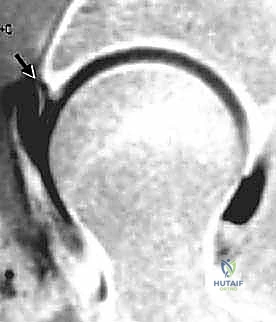

- الرنين المغناطيسي مع الصبغة المفصلية (MR Arthrogram): وهو المعيار الذهبي لتشخيص تمزقات الشفا الحقي وتلف الغضاريف. يتم حقن صبغة داخل المفصل قبل التصوير لإبراز أي تسرب للصبغة عبر التمزقات.

- الأشعة المقطعية ثلاثية الأبعاد (3D CT Scan): تُستخدم أحياناً للتخطيط الجراحي الدقيق وتشكيل نموذج ثلاثي الأبعاد للتشوهات العظمية.